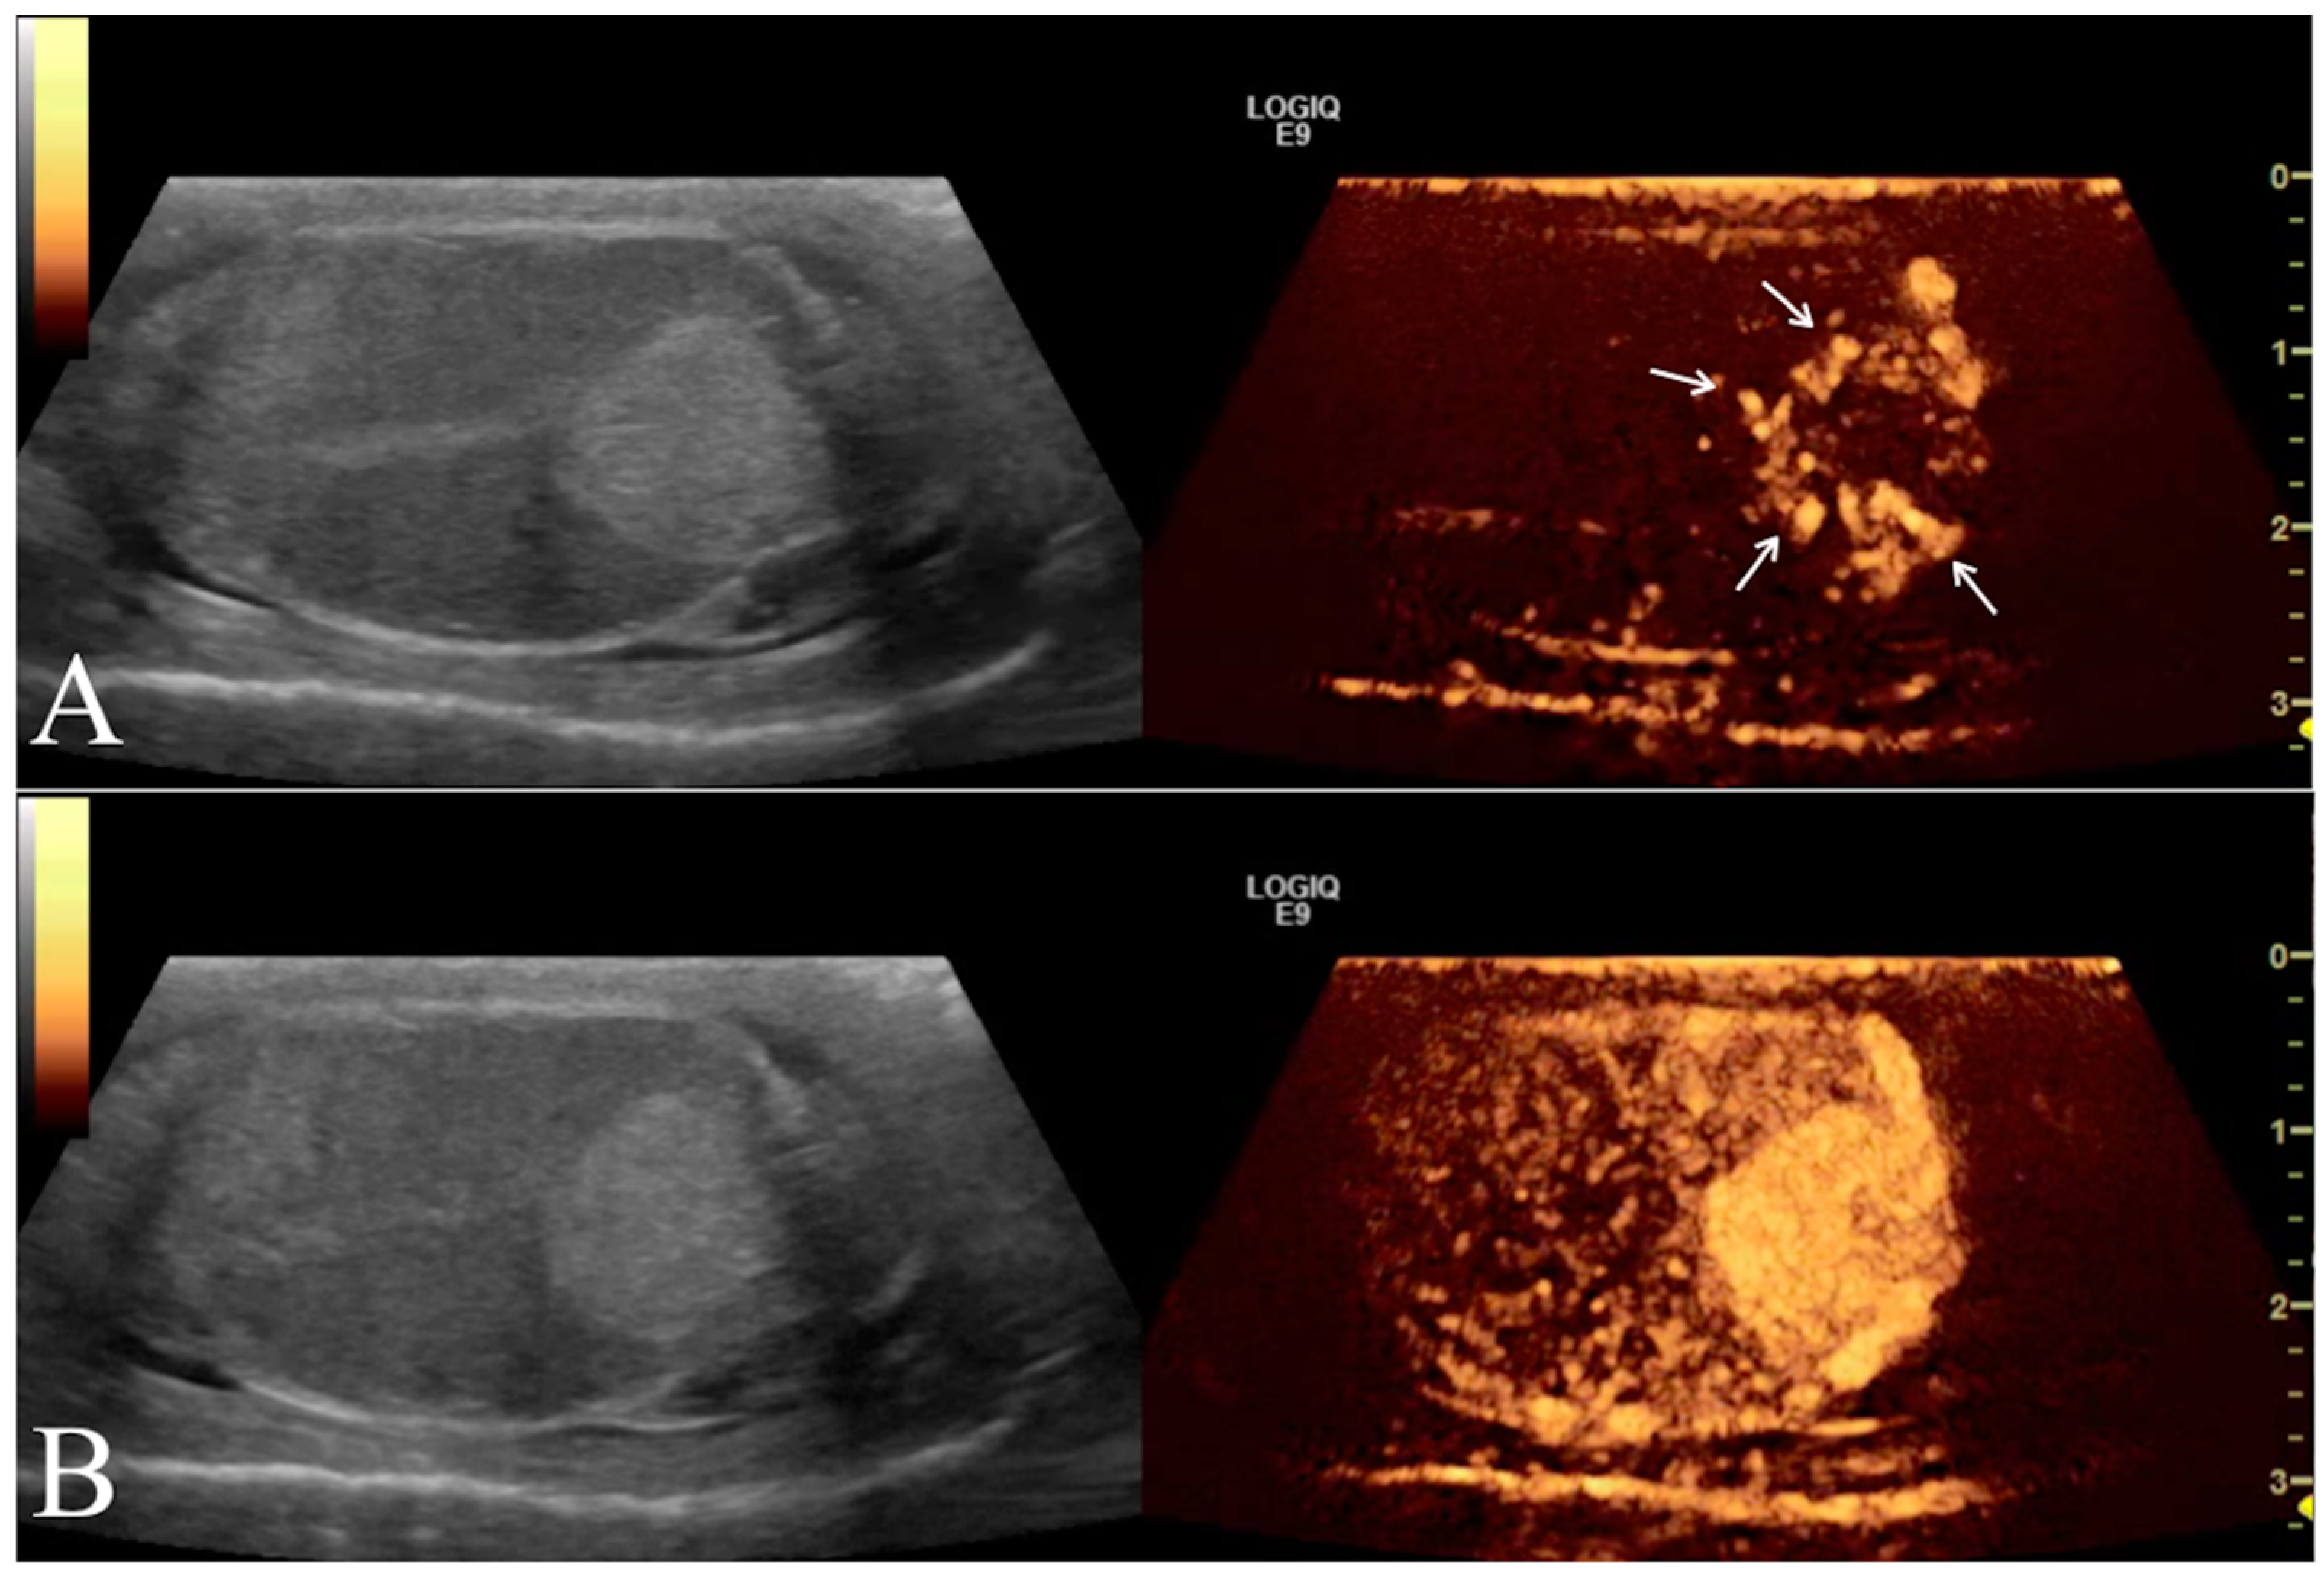

Contrast enhancement patterns during the distribution phases were first evaluated qualitatively for each testicle to assess the following parameters compared to normal testicular parenchyma: (i) arrival time of contrast medium into the lesion (early or late); (ii) wash-in enhancement (homogeneous or inhomogeneous; (iii) intensity of contrast (hyperenhanced, isoenhanced, or hypoenhanced) (Figure 4).

Figure 4. Left testicle leydigoma of a 11 year old Italian Mastiff (the same of Figure 2). The left panel shows the sagittal B-mode ultrasound highlighting a focal hyperechoic nodule with homogeneous echotexture and regular margin. Representative contrast-enhanced ultrasound images of different contrast distribution phases are represented in the right panels. After 16 s from contrast injection it is possible to appreciate an early distribution of the contrast within the lesions (Arrows) compared to the surrounding parenchyma (A). Later (25 s) the contrast medium distributes homogeneously within the lesion that remain hyperenhanced compared to the normal testicle (B).